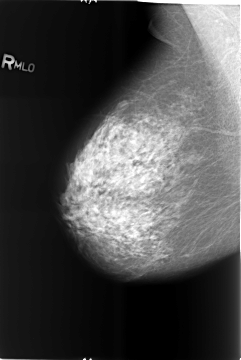

Volume: benign_without_callback_02 Case: B-3427-1

B_3427_1.RIGHT_MLO

RIGHT_MLO LINES 5752 PIXELS_PER_LINE 3848 BITS_PER_PIXEL 12 RESOLUTION 50 NON_OVERLAY

FILE: B_3427_1.LEFT_MLO.OVERLAY

TOTAL_ABNORMALITIES 5

ABNORMALITY 1

LESION_TYPE CALCIFICATION TYPE LARGE_RODLIKE-ROUND_AND_REGULAR DISTRIBUTION REGIONAL

ASSESSMENT 2

SUBTLETY 5

PATHOLOGY BENIGN_WITHOUT_CALLBACK